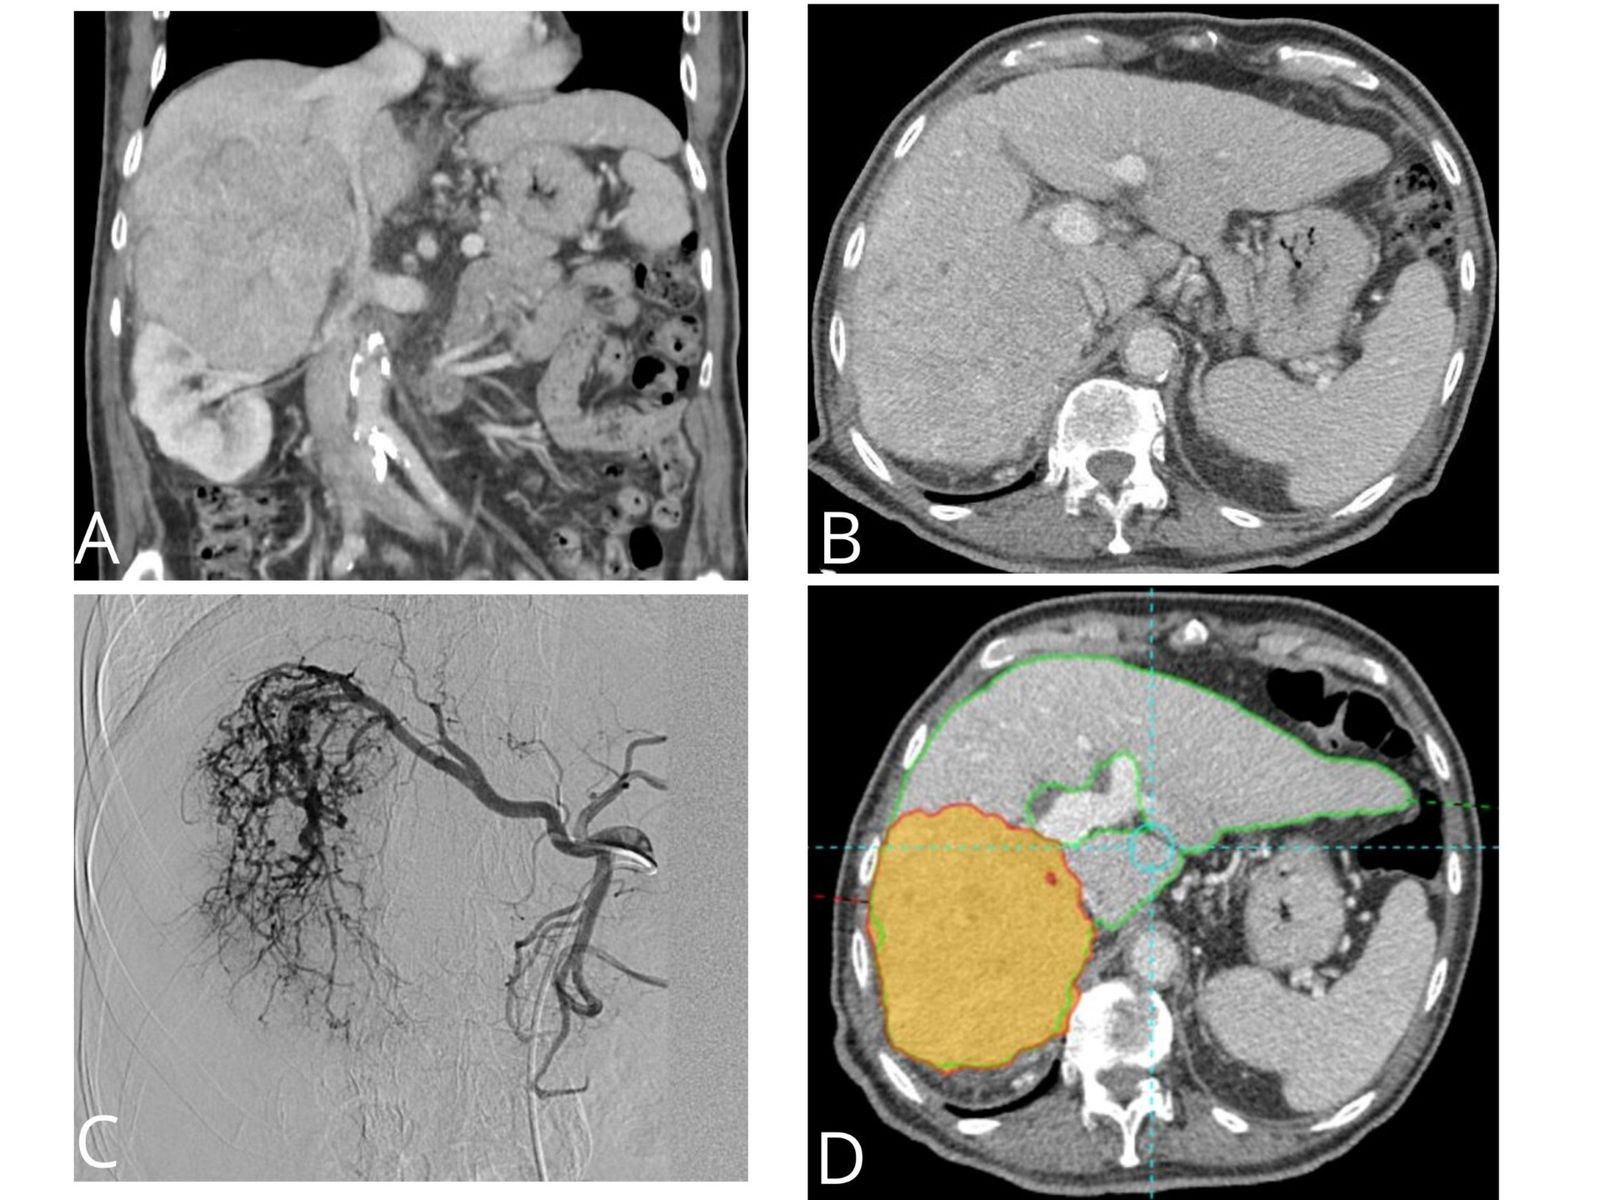

“La radioembolización es una terapia dirigida que consiste en que millones de microesferas de cristal radioactivas con itrio-90 producen una ablación intravascular en el lecho de la lesión”, matiza el doctor, quien indica que “estas microesferas del grosor de un cabello humano se dirigen directamente al tumor hepático a través de la arteria hepática, donde se introducen por medio de un catéter”.

“Las microesferas fluyen directamente hacia el tumor a través de los vasos sanguíneos del propio cáncer y se alojan permanentemente en el mismo y debido a que el procedimiento incide directamente en el tumor, la radiación destruye las células del cáncer con un impacto mínimo sobre el tejido hepático normal adyacente”, afirma.

Además, el especialista añade que “las microesferas seguirán emitiendo radiación durante varias semanas y es una terapia que también se puede utilizar para la reducción del estadío tumoral con el fin de que estos pacientes puedan someterse a una cirugía o trasplante”.